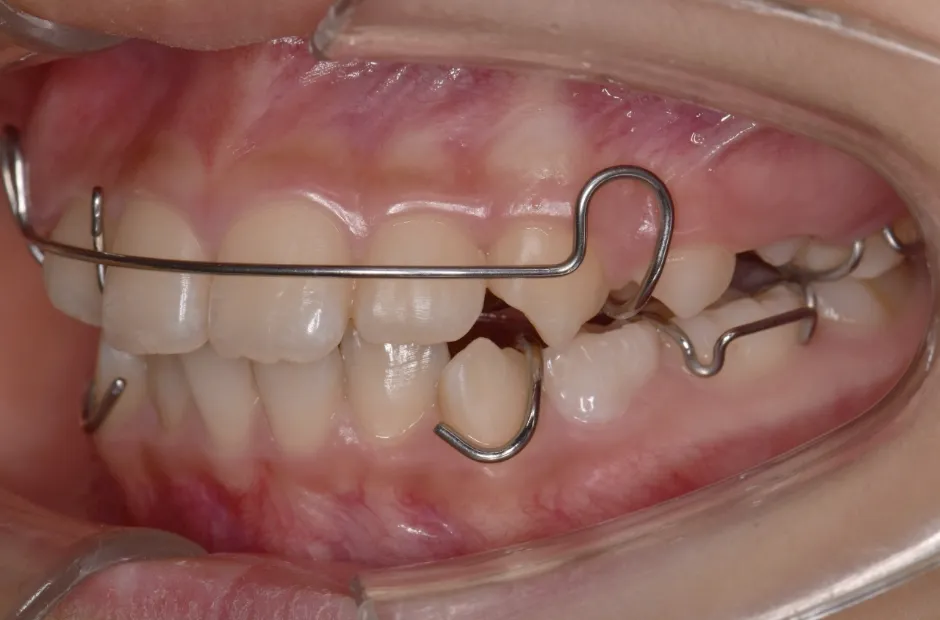

反対咬合

| 診断名・主訴 | 前歯反対咬合 |

|---|---|

| 年齢・性別 | 12歳・男性 |

| 治療期間・回数 | 1年半 18回 |

| 治療に用いた主な装置 | リンガルアーチ(前方誘導弾線) |

| 抜歯部位 | なし |

| 治療費 | 35万円(税抜) |

| リスク・副作用 | 装置による違和感・疼痛・歯肉退縮・歯根吸収・虫歯のリスクなど |

治療中